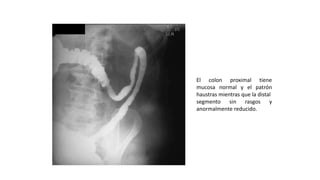

El colon proximal tiene

mucosa normal y el patrón

haustras mientras que la distal

segmento sin rasgos y

anormalmente reducido.